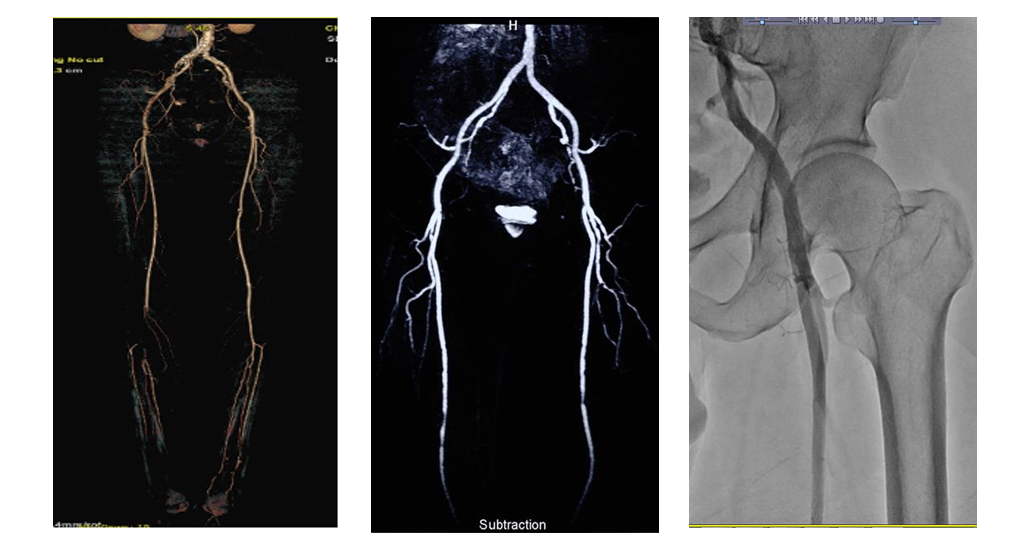

4. 정맥조영술 (Venography)

과거에는 정맥류 진단의 표준이었으나, 현재는 초음파가 대부분을 대체했습니다.

그러나 복잡한 정맥 질환이거나 수술 전 해부학적 정보가 더 정밀하게 필요한 경우 제한적으로 사용됩니다.

검사 방법

- 발등 정맥 등에 조영제를 주입한 뒤, 엑스레이나 CT, MRI를 촬영하여 정맥의 모양과 혈류를 관찰합니다.

사용 목적

- 심부정맥 폐쇄 또는 협착 여부 확인

- 복잡한 해부학적 구조 파악

- 초음파로 확인이 어려운 깊은 부위 정맥의 병변 확인